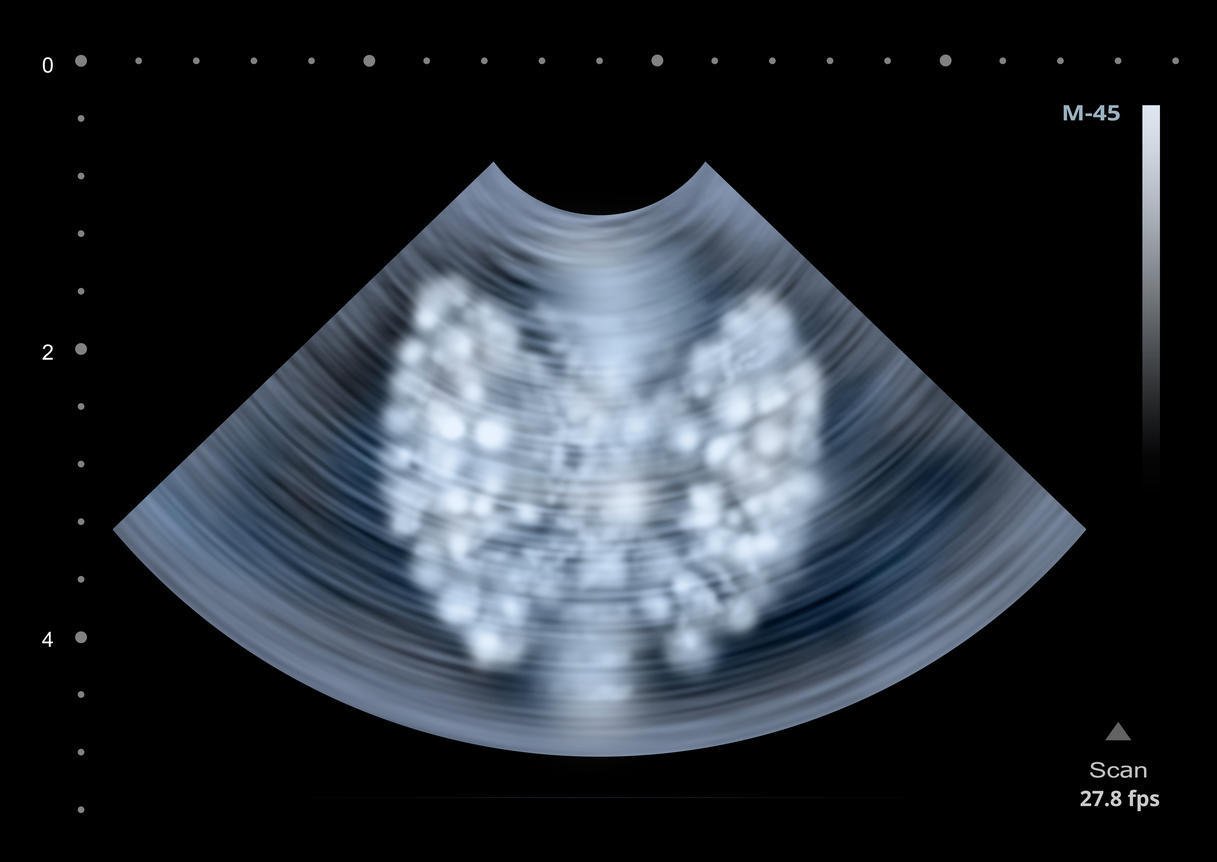

échographie de l'illustration de la glande thyroïde humaine

La glande thyroïde a la forme d'un papillon. Chaque "aile" du papillon, appelée lobe, est constituée de trois faces, trois bords et deux pôles. Le pôle supérieur est en rapport avec l'artère thyroïdienne supérieure, alors que le pôle inférieur est en rapport avec les veines thyroïdiennes inférieures. Lorsqu'un nodule se développe sur l'un des pôles, on parle de nodule polaire de la thyroïde. Plus que l'emplacement du nodule, c'est son importance et son caractère bénin ou malin qui vont influencer la prise en charge.